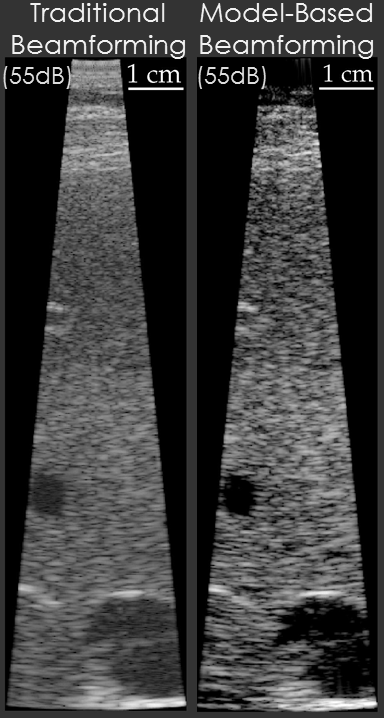

Example results are shown below for our model-based beamformer applied to in vivo human data.

In the first example, the data beamformed using traditional methods has a “hazy” appearance that is common in in vivo imaging. The image beamformed using the model-based beamformer appear significantly sharper. The result is compelling, but a common criticism is that the same result could be obtained by changing the compression on the ultrasound scanner. To address this criticism another set of example data is shown. The second set of example data shows 3 images of the same structure in the same patient. When the data from the patient is beamformed using traditional methods the bile duct is not visible. When the data is beamformed using a model-based approach the bile duct is present in each case. The notable aspect of this example is that changing the system compression would not enable the visualization of the bile duct.